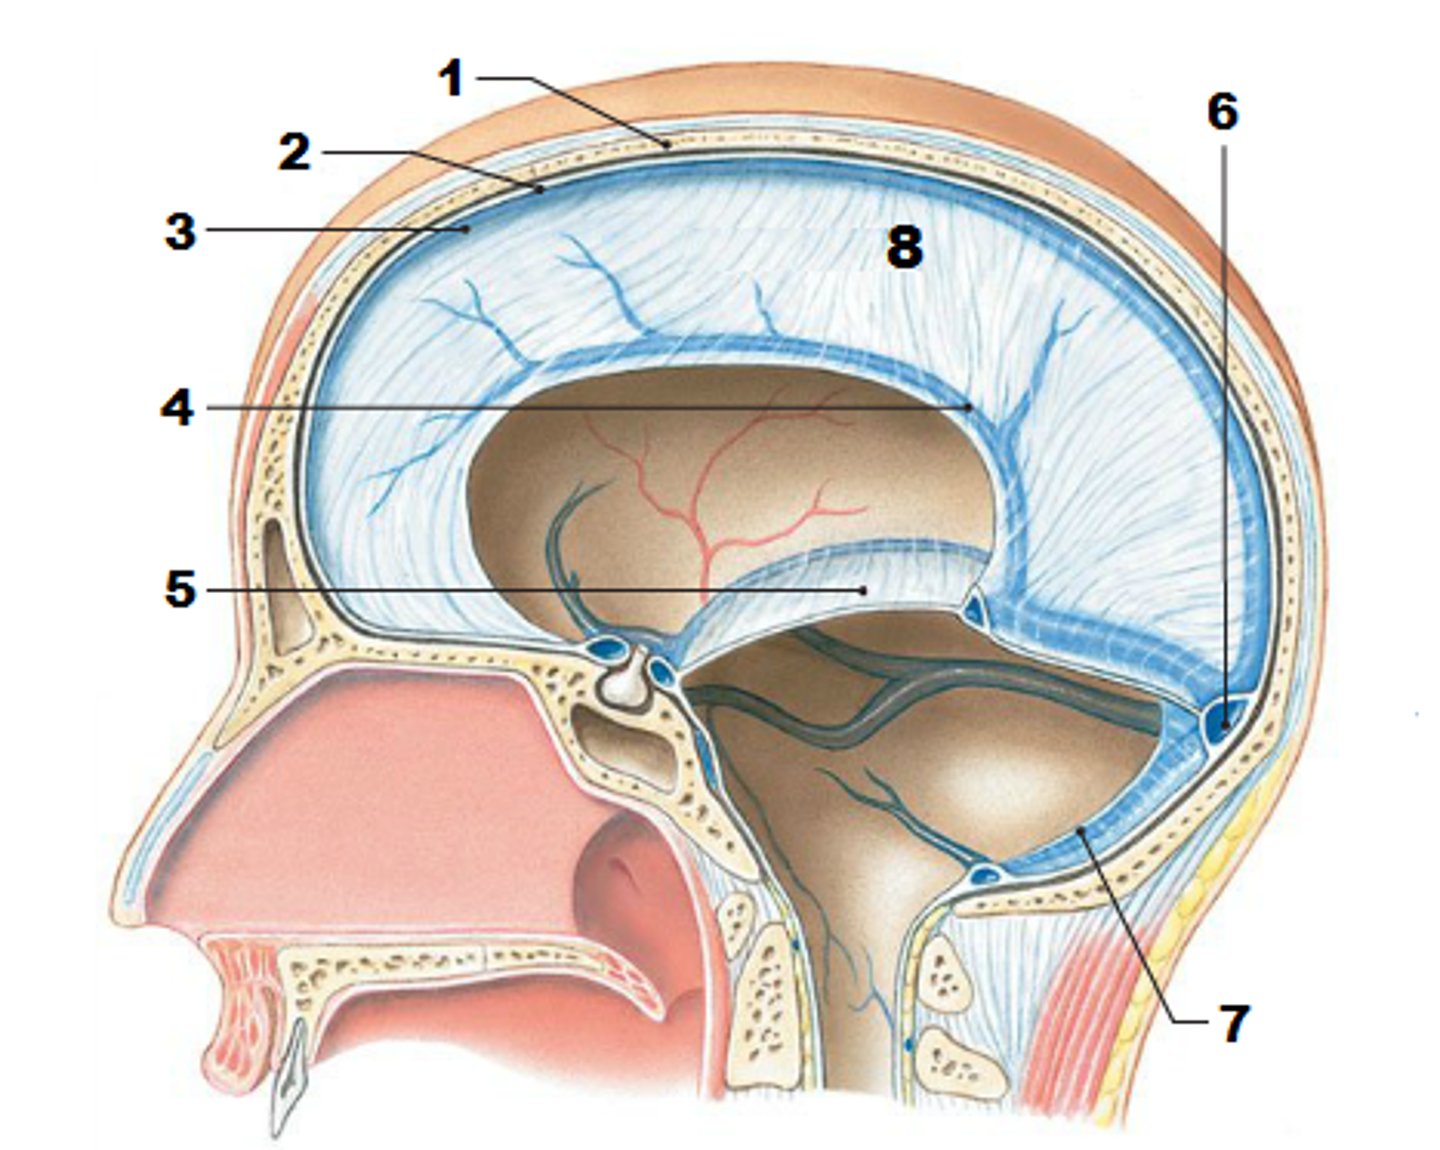

3 layers make up the meninges

dura mater, arachnoid mater, pia mater

dura mater

outer periosteal layer & inner meninges layer

periosteal and meningeal

two layers of dura mater

falx celebri

large, sickle-shaped, separates the cerebral hemispheres

tentorium cerebelli

2nd largest, crescent-shaped, separates cerebrum (occipital lobes) from cerebellum (arrow #5)

falx cerebelli

seperates the two hemispheres of the cerebellum. it lies inferior to the tentorium cerebelli, separating cerebellar hemispheres (arrow #7)

diaphragm sellae

smallest infolding covering pituitary gland & sella turcica

arachnoid

middle layer of meninges; weblike appearance that attaches it to deepest layer

arachnoid trabeculae

superior sagittal sinus

subdural space

space between dura mater and arachnoid mater

subarachnoid space

skin of scalp

arachnoid mater

pia mater

the delicate innermost membrane enveloping the brain and spinal cord.